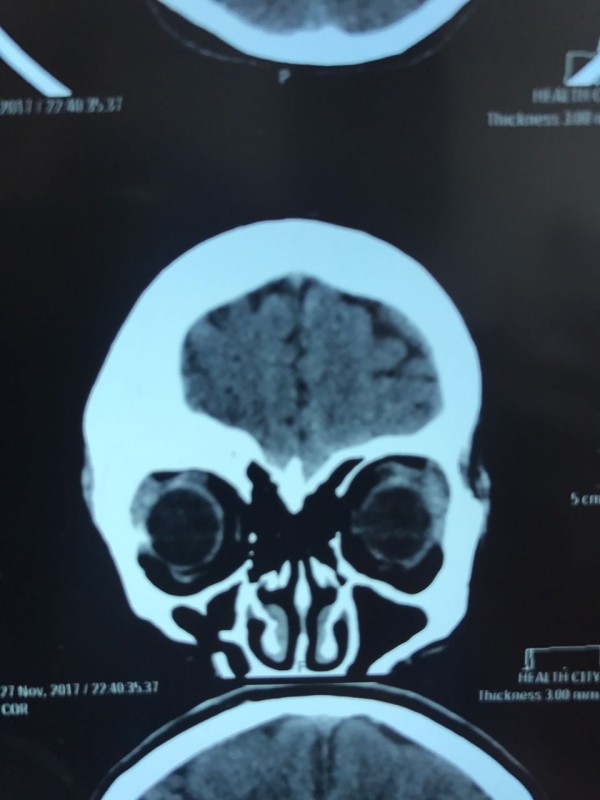

Как рассказал врач-нейрохирург городской клинической больницы № 7 Алматы Константин Ли, предварительный диагноз пациента - "фиброзная дисплазия лобной кости справа", то есть опухолевое поражение костей черепа. По его словам, сложность и уникальность операции в том, что опухоль плотно соприкасалась со зрительным нервом.

"Компьютерная томография показала, что костная опухоль поражала лобную кость и "крышу" орбиты глаза, которая, в свою очередь, сдавливала глазное яблоко. Чтобы убрать опухоль, потребовалось немало времени. Наша задача была сохранить глазное яблоко, зрительный нерв и сосуды. Если неправильно провести операцию и неправильно закрыть дефект, то в последующем это может привести к эстетической неполноте и асимметрии лица. Уникальность еще и в том, что в операции применялась 3D-стереолитография, которая делается только в Алматы", - рассказал он.

Снимок сделан до операции. Фото предоставлено Константином Ли